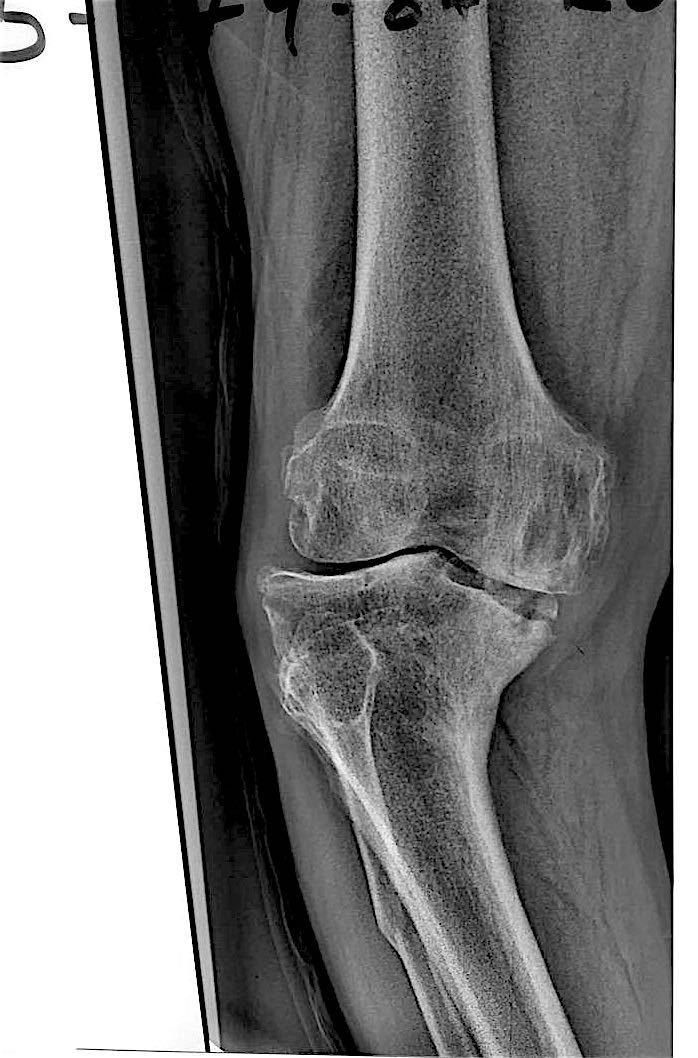

Больной З. 72 года. Диагноз: посттравматический деформириующий правосторонний гонартроз, genu valgum.

Сделано тотальное эндопротезирование коленного сустава, костная аллопластика материалом «Лиопласт».